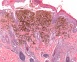

On examination she has multiple scaly plaques across her trunk, arms and legs, consistent with psoriasis (see Figure 1).